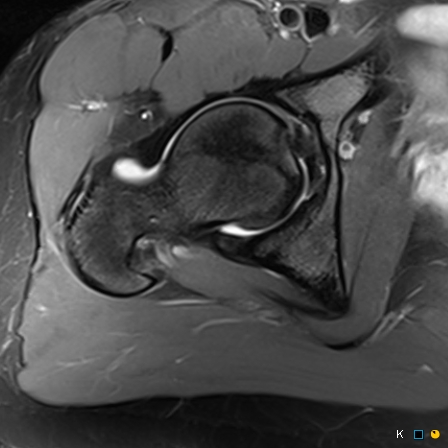

Figure 2 for case reverse slipped upper femoral epiphysis

Figure 2